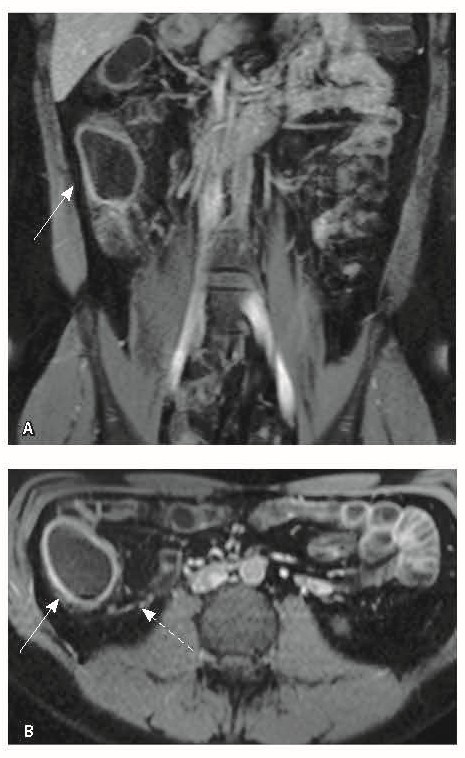

При мультиспиральной компьютерной томографии органов брюшной полости визуализировалась картина диффузного утолщения стенки толстой кишки с умеренным утолщением брыжейки и минимально выраженными явлениями лимфаденопатии в брыжейке (рис. 1).

Рис. 1. Мультиспиральная компьютерная томография органов брюшной полости с внутривенным введением контрастного вещества (йомепрол 350–100 мл), артериальная фаза: А – фронтальная проекция, Б – аксиальная проекция. Стрелками указано диффузное утолщение стенки толстой кишки и брыжейки

Назначена ГИБТ адалимумабом (препарат Хумира) по стандартной схеме 160 мг п/к (неделя 0), 80 мг п/к (неделя 2) с последующим плановым поддерживающим режимом 40 мг п/к каждые 2 недели. Через 9 месяцев установлена эндоскопическая ремиссия, однако сохранялась концентрация фекального кальпротектина более 2000 мкг/г. Через год жалобы возобновились, тогда же впервые была выявлена задняя анальная трещина. Выполнена магнитно-резонансная энтерография, обнаружены воспалительные изменения, характерные для БК (рис. 2 и 3).

Рис. 2. Магнитно-резонансная энтерография, Т2-взвешенное изображение: А, В – фронтальная проекция; Б – аксиальная проекция. Наблюдается отсутствие гаустрации в восходящем отделе ободочной кишки, утолщение ее стенки до 5 мм (стрелка), снижение магнитно-резонансного сигнала от прилежащих отделов клетчатки, ее неоднородность (пунктирная стрелка), увеличение лимфатических узлов до 6 см в диаметре по ходу сигмовидной кишки (стрелки)